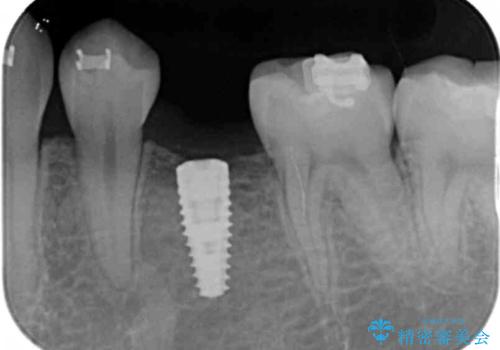

歯がなかった時期に隣の歯が移動してすき間があったため、部分的な矯正治療を行い、インプラントを入れるすき間を確保しています。

矯正治療で歯を移動して得られたすき間はインプラントのクラウンで動かないようにできるためです。

保定が不要という点におきましては、部分矯正と補綴(被せ物)治療は非常に相性がよく、得られるメリットも大きいといえます。